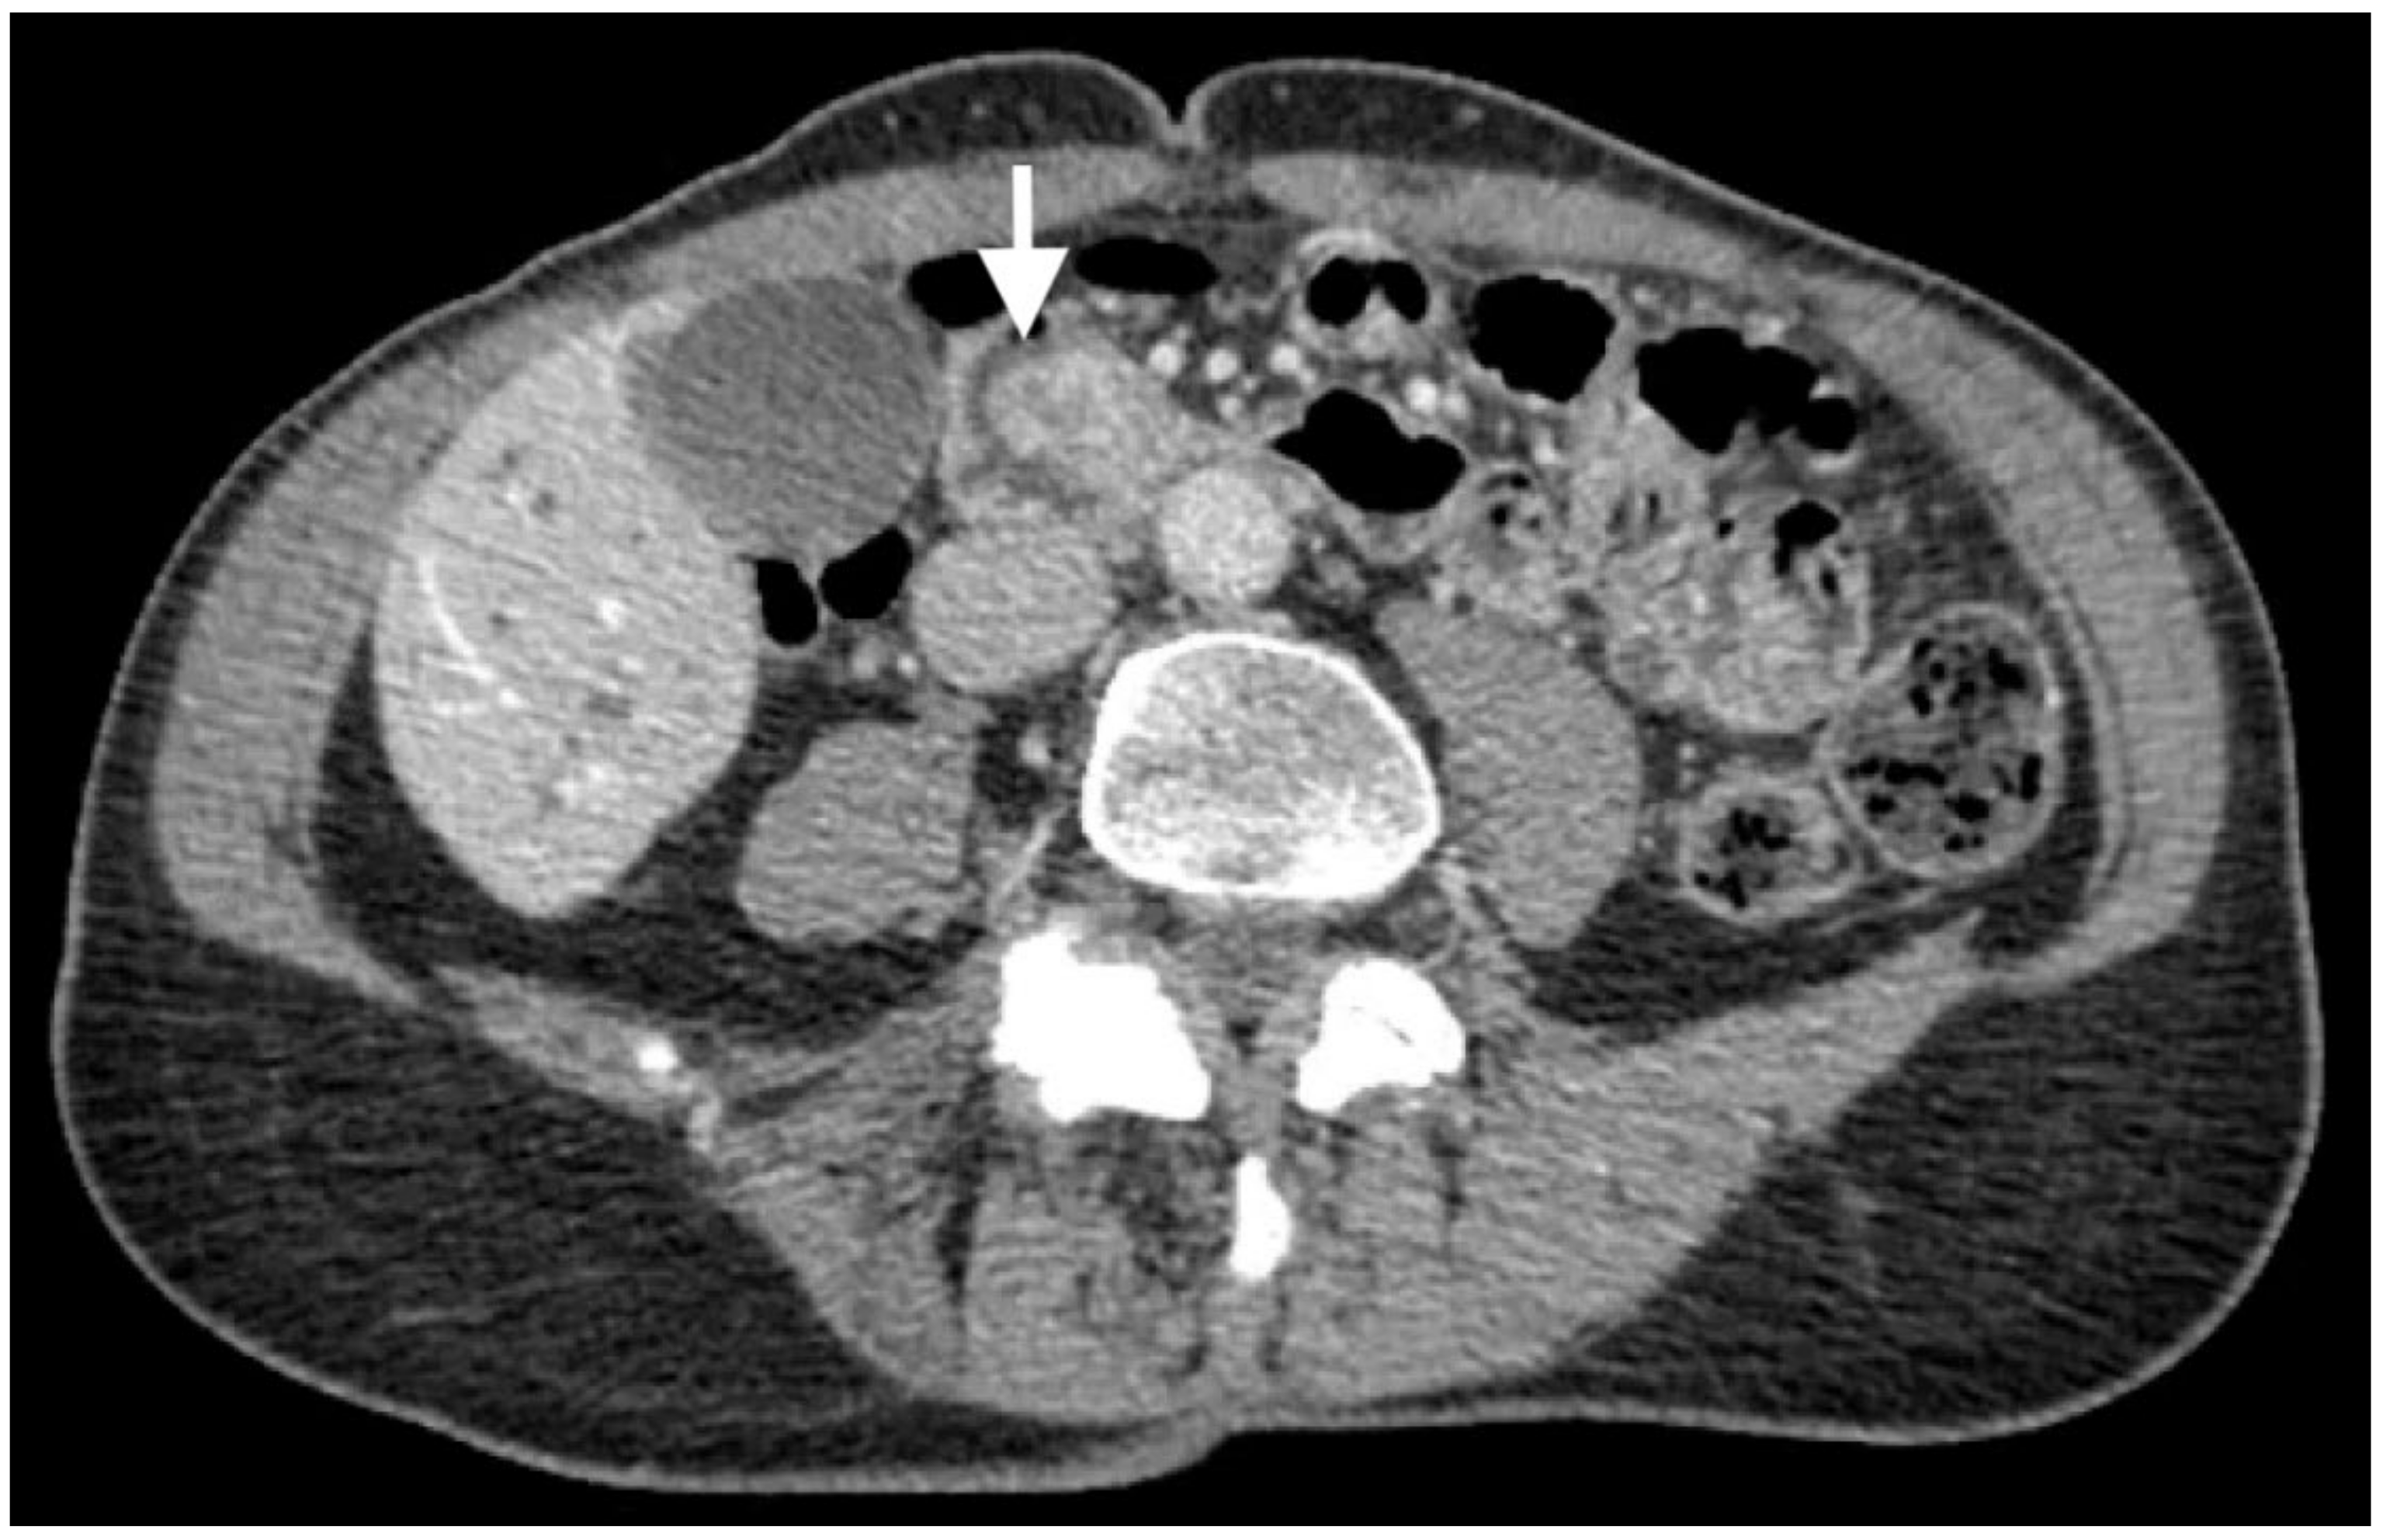

2. Case Description